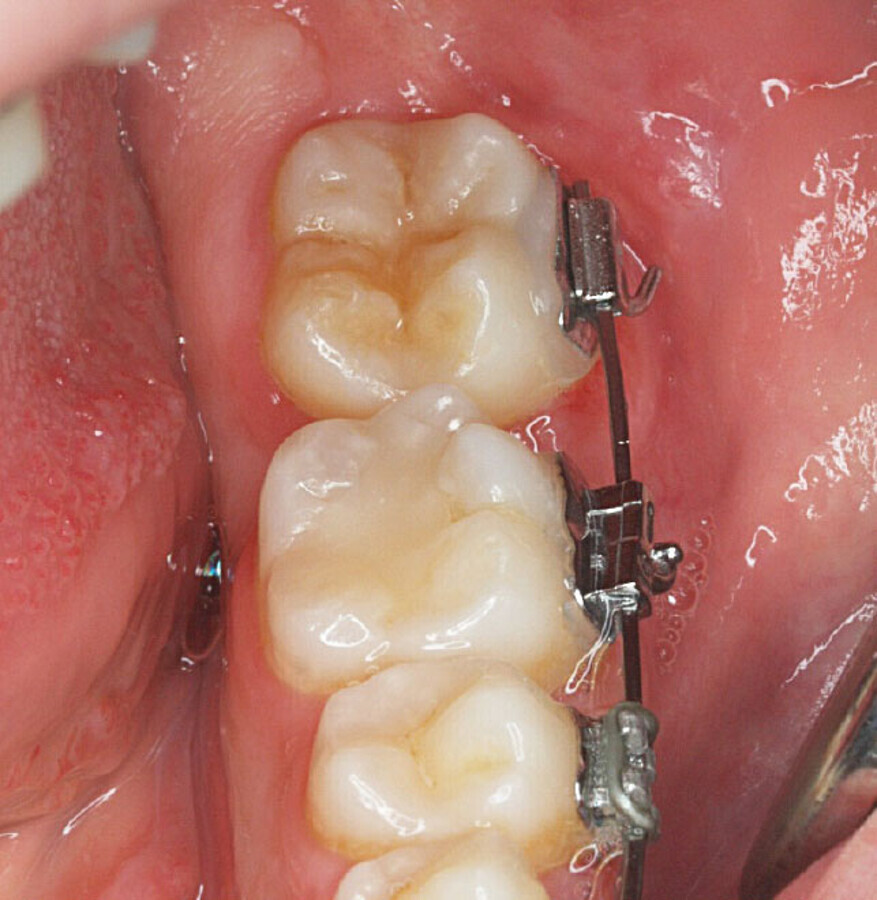

Control coil spring abierto (diente 38 exodonciado).

Aproximadamente 6 meses después, se prepara un anclaje esquelético con un tornillo de titanio autoperforante (D2.0 / L 12mm, Jeil Medical Corporation). Estos tornillos son más indicados para fijar injertos en bloque. Este anclaje permite enderezar el segundo molar por completo. En una primera fase, se tracciona desde el tornillo a un botón colocado en la cúspide distolingual del diente 37 con cadeneta elástica. Una vez el diente 37 está “desenclavado”, se termina de enderezar, cementando estratégicamente brackets y tubos de cementado directo y utilizando arcos elásticos NiTi.